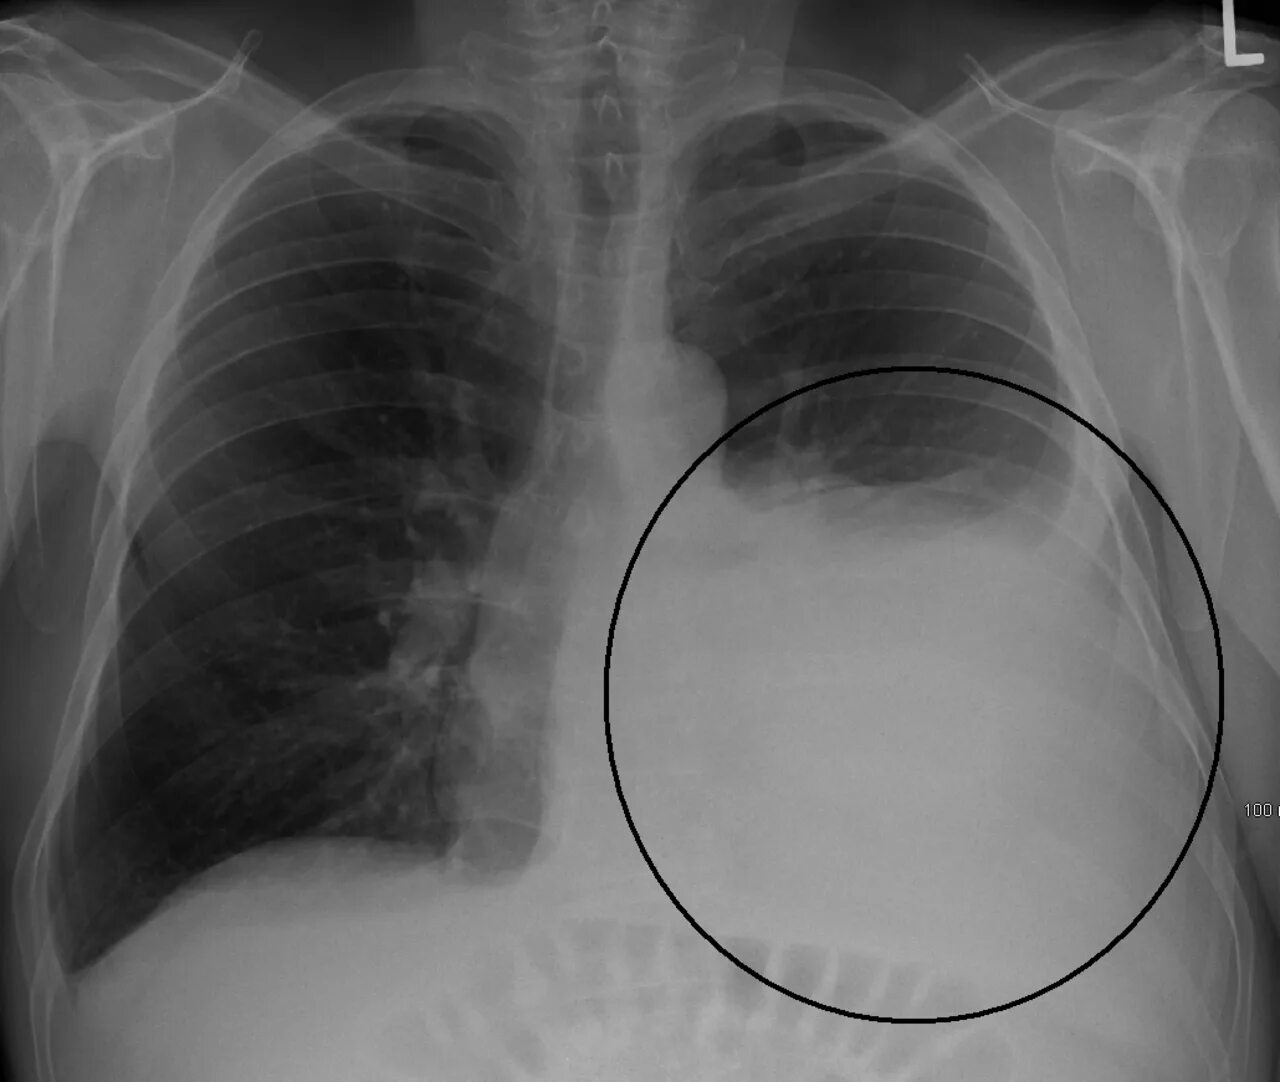

Закончился воздух в легких